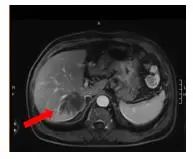

2021-12-21(治疗2周期后) 腹部增强MRI:胃壁增厚较前减轻,腹腔多发肿大淋巴结较前减小、较大者直径约1.6cm,肝脏病灶较前缩小、6.9*5.5cm,评效SD(缩小18%)

图3.治疗2周期后腹部增强MRI影像图

2022-02-04(治疗4周期后)胃壁增厚、腹腔多发肿大淋巴结无明显变化;肝脏病灶继续较前缩小、4.6*3.1cm,部分转移病灶消失,评效SD(缩小27%)

图4.治疗4周期后腹部增强MRI影像图